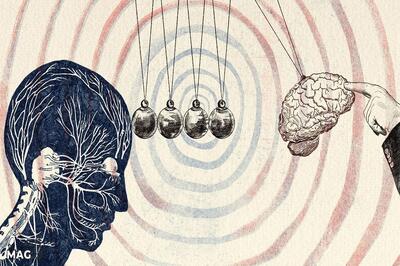

روشی امیدوارکننده برای کاهش رشد سرطان روده بزرگ و افزایش شانس بقا

باشگاه خبرنگاران جوان - تیمی از دانشمندان در کره جنوبی کشف کردهاند که مهار یک پروتئین خاص در سلولها میتواند رشد سرطان روده بزرگ را به طور قابل توجهی کُند کند.

این مطالعه نشان داد که غیرفعال کردن ژنی به نام NSMF، که مسئول تولید پروتئینی است که به سلولهای سرطانی کمک میکند تا با تقسیم سریع سازگار شوند، منجر به چیزی میشود که آنها آن را "پیری سلولی برگشتناپذیر" در تومورها توصیف کردند.

به طور معمول، سلولهای سرطانی به سرعت تقسیم میشوند و پروتئین NSMF باعث آسیب به DNA و ظهور جهشهای جدید میشود. اما هنگامی که این ژن در آزمایشهای آزمایشگاهی و در موشها خاموش شد، رشد تومور کند یا به طور کامل متوقف شد.

در یک آزمایش روی موشها، مهار NSMF منجر به کاهش قابل توجه رشد تومورهای روده شد و طول عمر حیوانات در مقایسه با موشهایی که ژن در آنها غیرفعال نشده بود، به طور متوسط ۳۳.۵ درصد افزایش یافت. دانشمندان هیچ آسیبی به سلولهای سالم روده مشاهده نکردند، که نشان میدهد این روش برخلاف شیمیدرمانی سنتی، تومورها را بدون آسیب رساندن به سلولهای طبیعی هدف قرار میدهد.

دانشمندان معتقدند که این یافتهها گامی امیدوارکننده به سوی توسعه درمانهای جدید است که میزان بقا را افزایش میدهد، اگرچه مطالعات بیشتری در انسان مورد نیاز است.

دکتر کیونگ-جین شین، متخصص سرطان در مؤسسه ملی علوم و فناوری اولسان (UNIST)، که رهبری این مطالعه را بر عهده داشت، گفت: «نتایج ما نشان میدهد که NSMF یک هدف امیدوارکننده است. با القای حالت پیری دائمی در سلولهای سرطانی، میتوانیم رشد تومور را بدون آسیب رساندن به بافت سالم به طور مؤثر متوقف کنیم.»

وی افزود که توسعه داروهایی برای مسدود کردن این پروتئین «میتواند یک رویکرد درمانی جدید» علیه سرطان ارائه دهد.